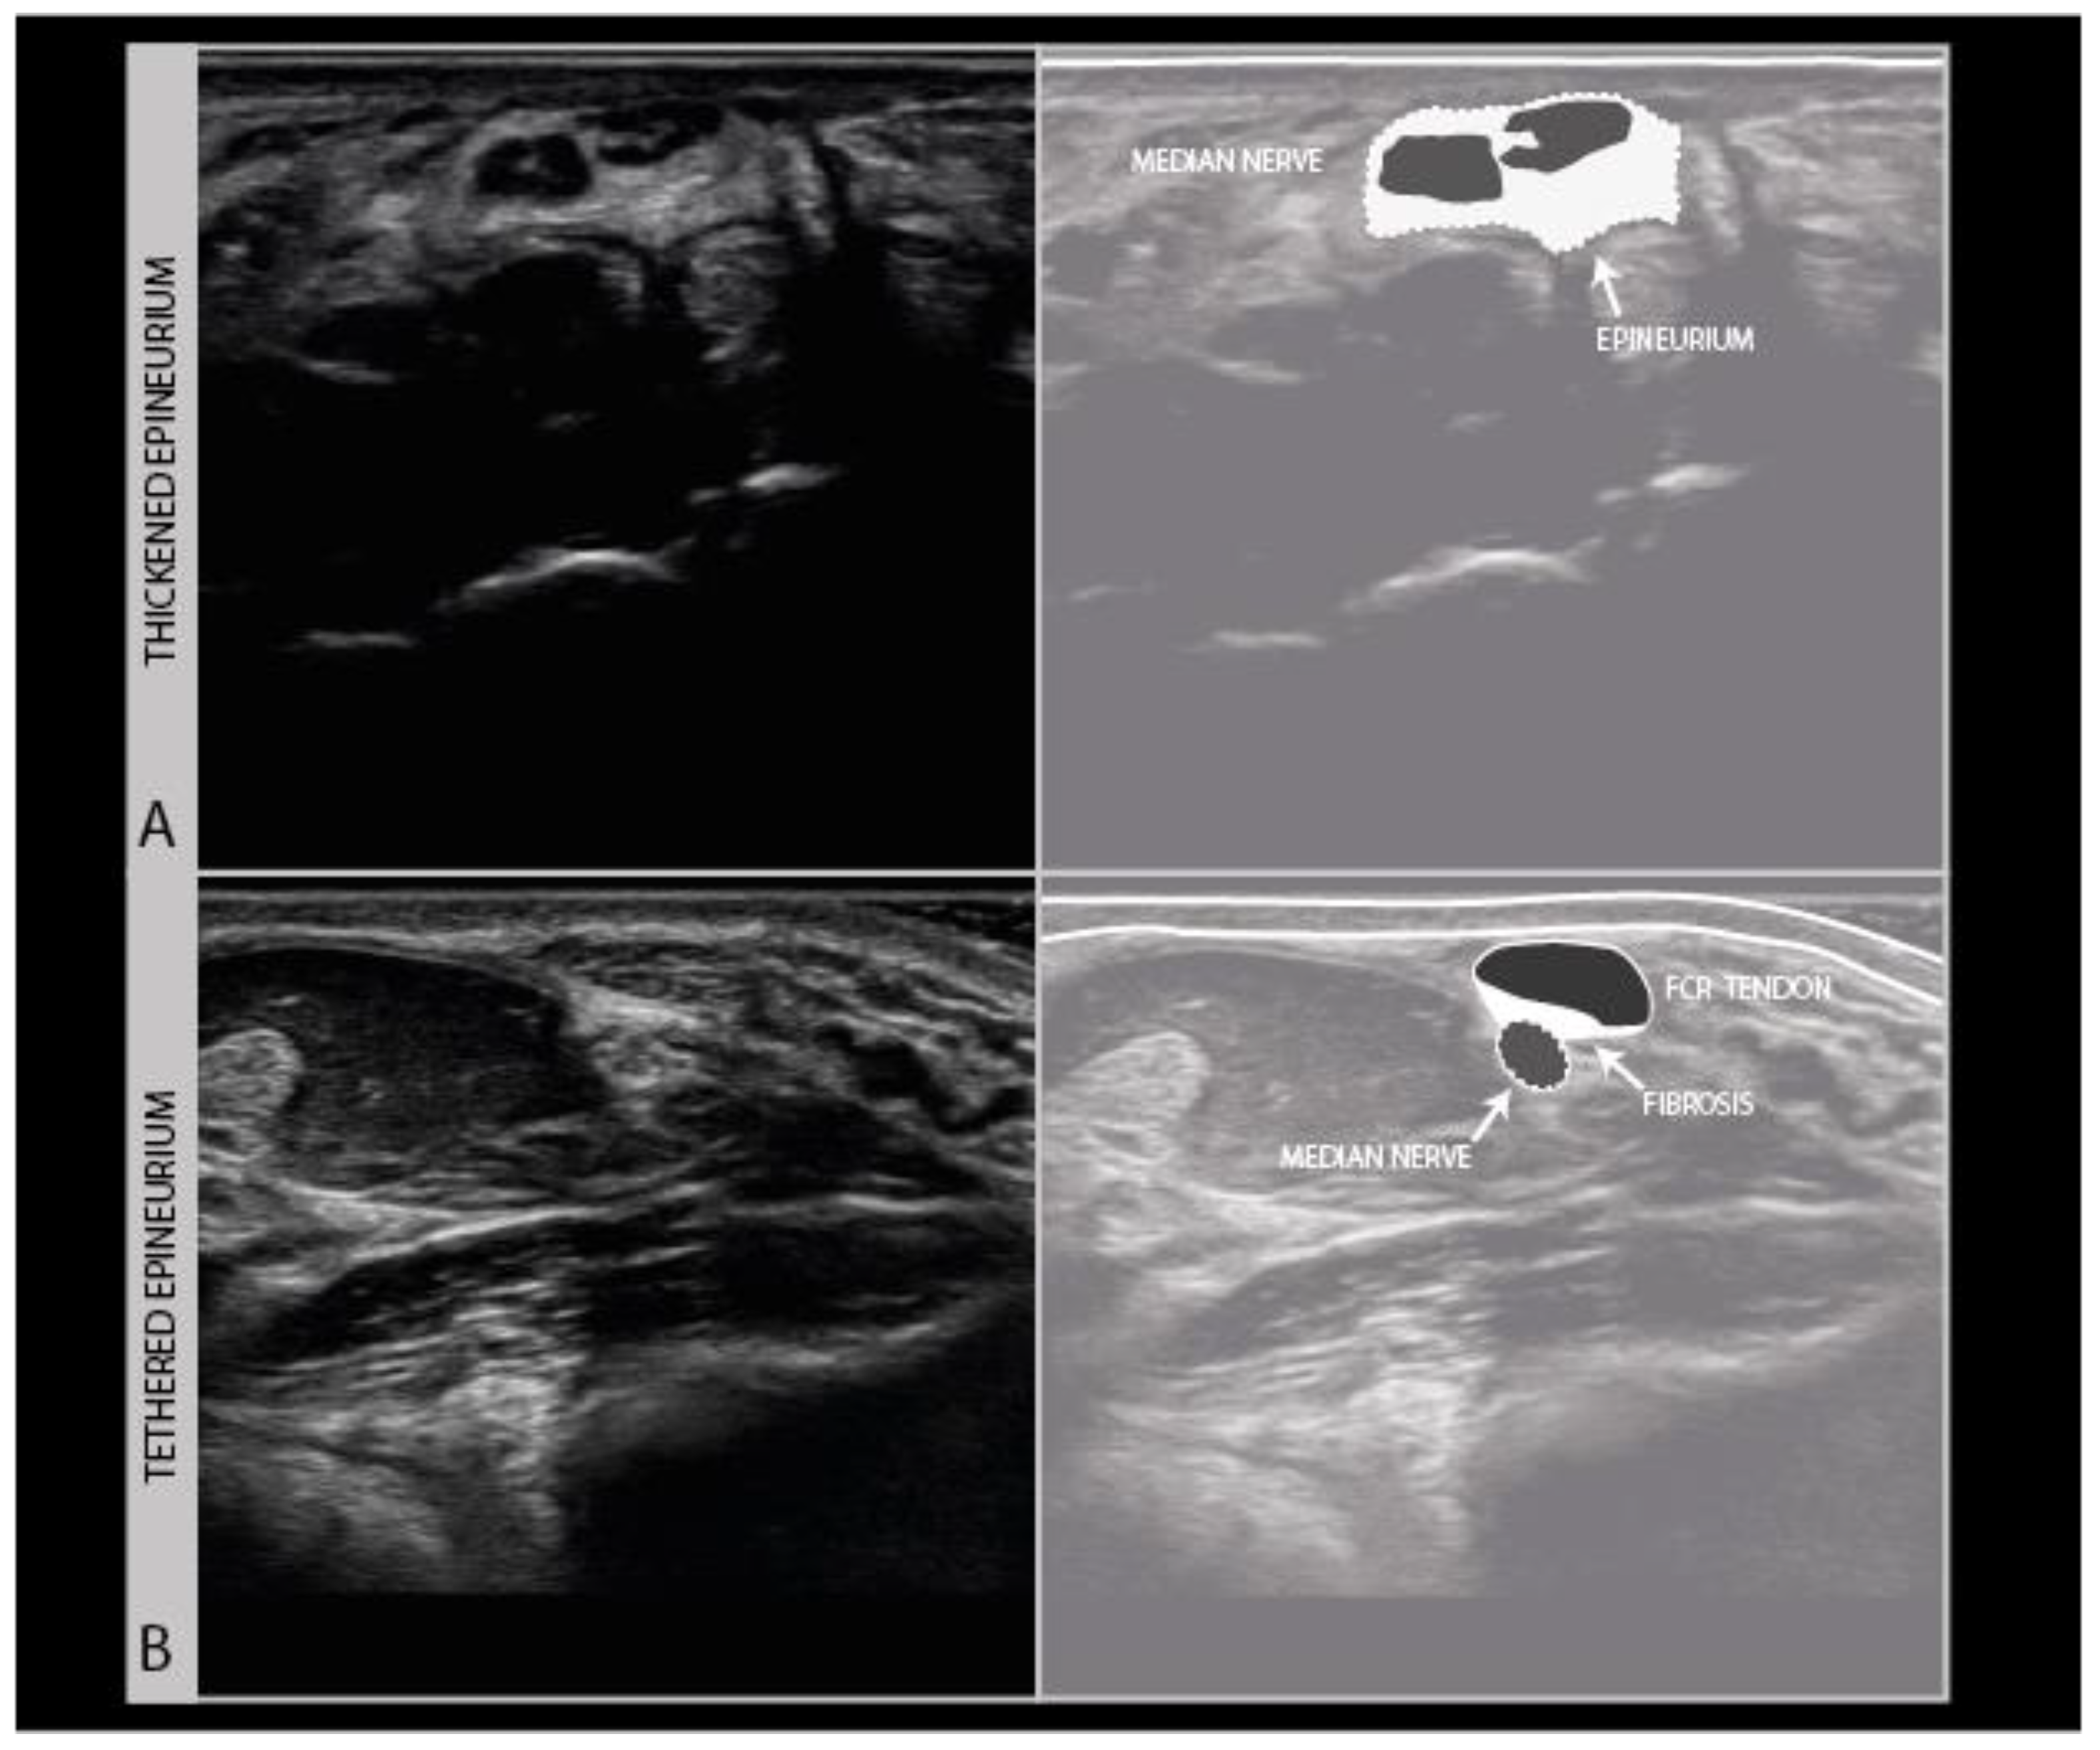

Scarring can also involve the nerve and its connective tissue ensheathing itself (Figure 9A), and can lead to a loss of nerve elasticity and adhesions to surrounding tissues (Figure 9B).

Figure 9.

Persistent median neuropathy with very thick epineurial rim and hypoechogenic, swollen nerve fascicles, in a female patient who underwent 30+ carpal tunnel release surgical procedures (A). Median nerve adhesion in the distal forearm; the superficial epineurium of the nerve is tethered to the flexor carpi radialis tendon sheath directly on top of the nerve (hyperechoic region between the tendon and nerve) (B).